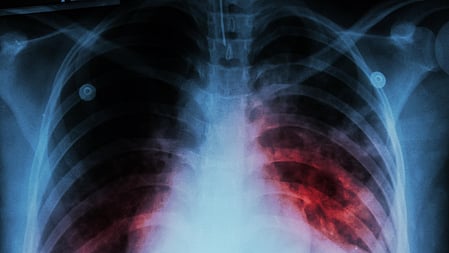

“However, these asymptomatic TB cases keep spreading the disease. The need is to screen all patients coming to a doctor or hospital for treatment of any disease to detect latent tuberculosis in them. This can be done by using portable X-ray machines. The silent carriers will continue to grow and spread the disease unless transmission is stopped through screening,” he said.